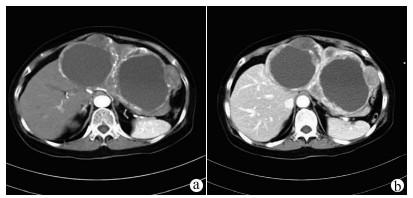

Recurrence after hepatectomy for primary gastrointestinal stromal tumor of the liver: A case report

Kangwei LIU, Xin GENG, Lei WANG, Cijun PENG

2021, 37(12): 2893-2895. DOI: 10.3969/j.issn.1001-5256.2021.12.031

Abstract(971) HTML (239) PDF (2357KB)(56)

Abstract: